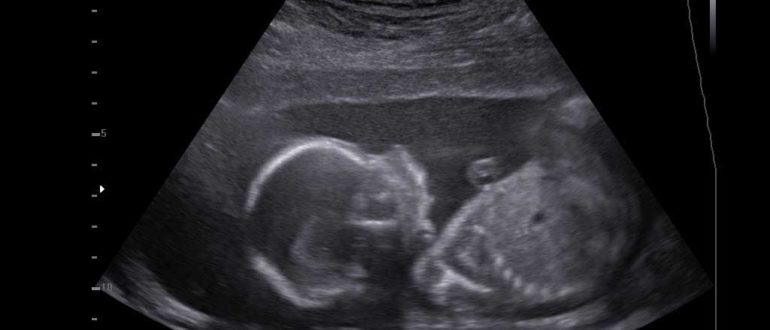

Узи в 21 неделю

Узи на 21 неделе беременности: что смотрят, норма, расшифровка 21 первая неделя – это середина беременности, можно сказать экватор. Начинается достаточно простой и благостный этап вынашивания ребенка. Будущая…